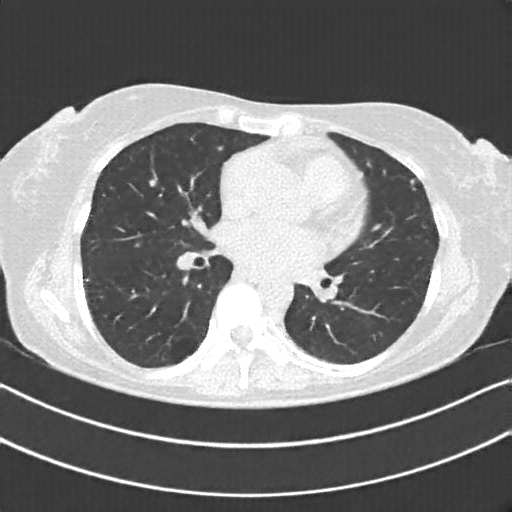

Reconstructed NATIVE CT scan (cycle consistency)

No window - Raw intensity values

Reconstructed NATIVE CT scan (cycle consistency)

Lung window (WL -600, WW 1500 → Low −1350, High +150)